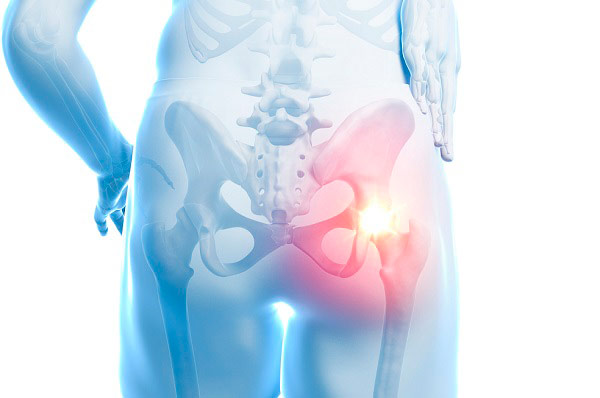

고관절은 엉덩이관절이라고도 불리우며, 보통 알고있는 골반위치에 있고, 공처럼 둥글게 생긴 대퇴골두가 글러브가 감싼듯한 모양으로 비구에 맞물려 있어요.

이렇듯 고관절은 오목하게 들어간 비구와 둥근 공모양의 대퇴골두로 이루어져 있으며 골반과 다리를 이어주는 우리 몸의 핵심 관절인데요. 그리고 고관절은 골반을 통해 전달되는 체중을 지탱해주고 걷기와 달리기같은 다리 운동들을 가능하게 해주는 관절이기도 해요.